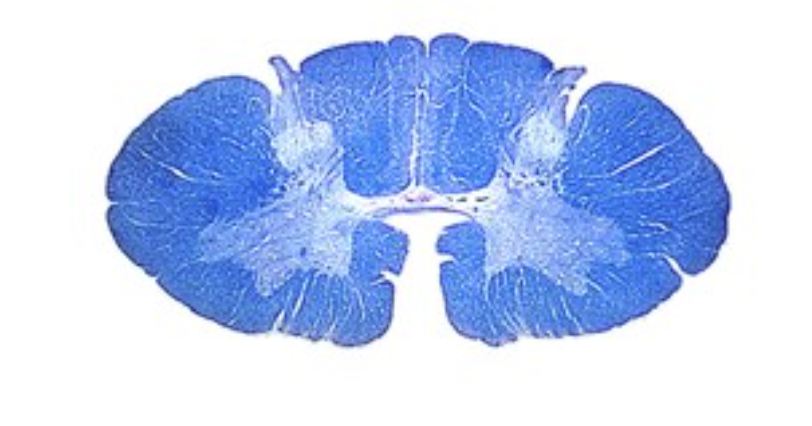

What level is this section?

cervical

Identify

denticulate ligament

ventral root

Spinal muscular atrophy is a disorder that results in a loss of anterior horn cells. What would be the expected clincal sign in patients?

profound muscle weakness, marked muscle hypotonia, inability to move muscles,loss of reflexes

Anterior spinal artery